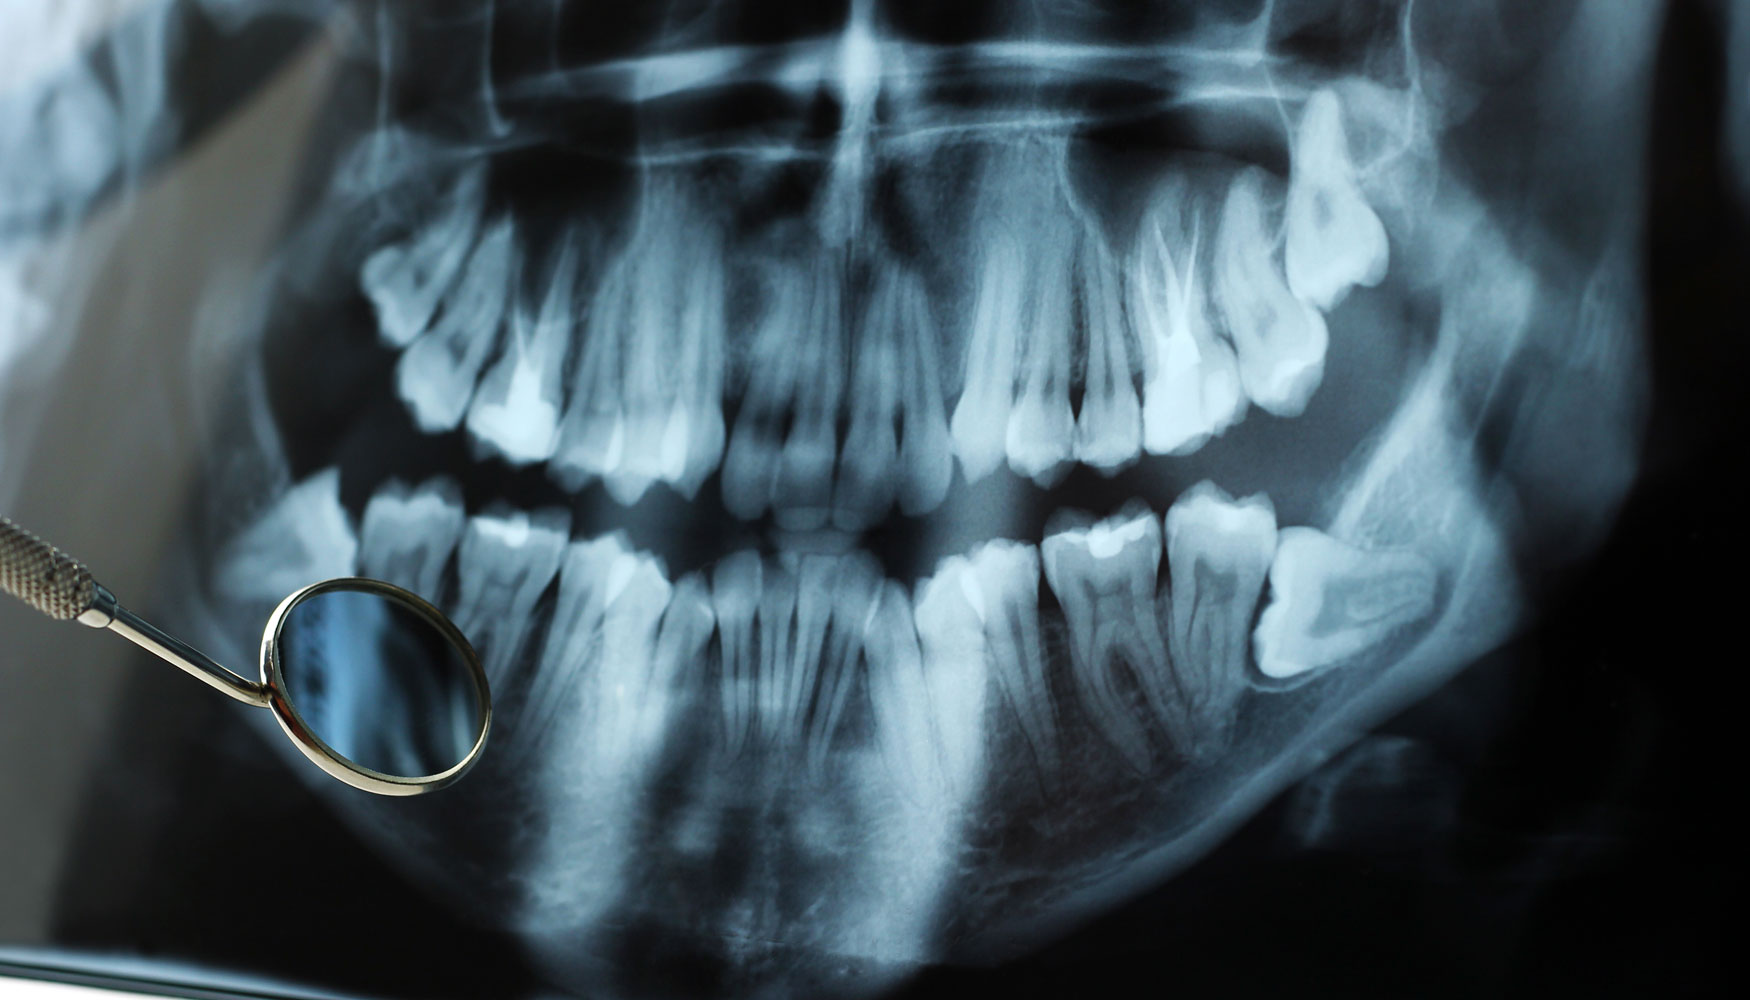

Panoramic X-ray Image Of Teeth And Mouth With Wisdom Teeth | Parkview

fountainhillsdentist.comwisdom teeth ray mouth panoramic back tooth

fountainhillsdentist.comwisdom teeth ray mouth panoramic back tooth

Impacted Wisdom Tooth: Dentist Recommended Treatment

idental.com.sgwisdom impacted tooth dental ray fully dentist molar symptoms space treatment

idental.com.sgwisdom impacted tooth dental ray fully dentist molar symptoms space treatment